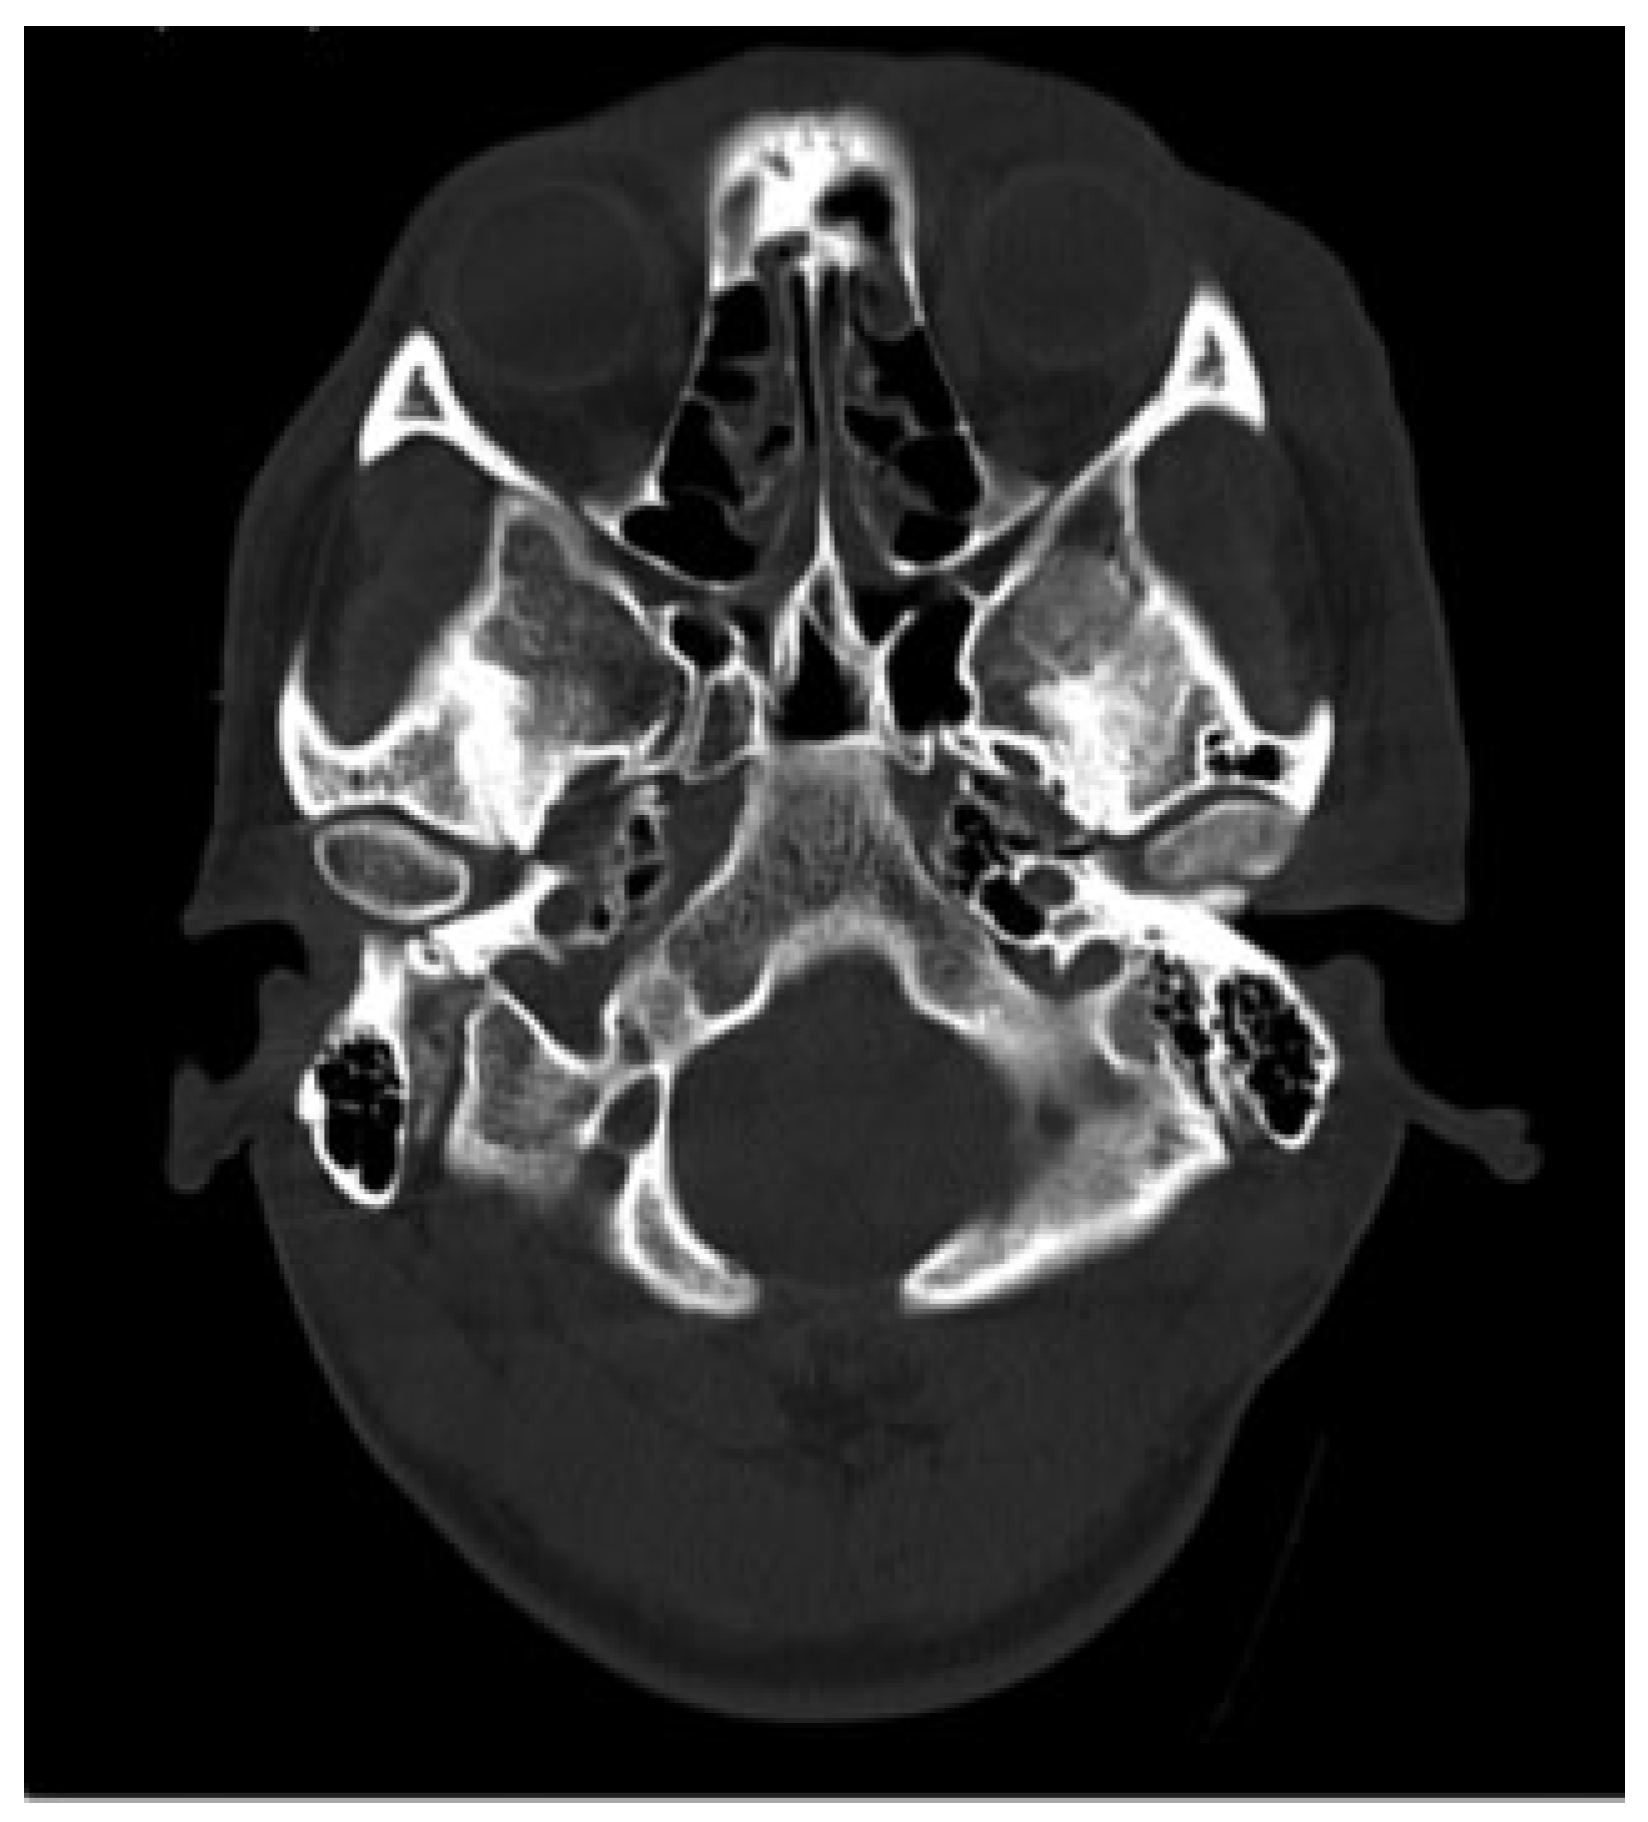

Examination revealed maximum mouth opening was 42 mm with 15 mm of anterior open bite upon closing. Computed tomographic (CT) scan that was taken immediately post-MVA shows no fractures to his facial skeleton and both condylar heads were located in the glenoid fossae ([

Figure 1]). He was subsequently sent for another CT scan to view the position of the condyles. Both condylar heads of the mandible were anteriorly dislocated from the TMJ fossae and were located at bilateral infratemporal fossae ([

Figure 1.

Computed tomographic scan immediately post–motor vehicle accident shows both condylar heads located in the glenoid fossa.

Figure 1.

Computed tomographic scan immediately post–motor vehicle accident shows both condylar heads located in the glenoid fossa.